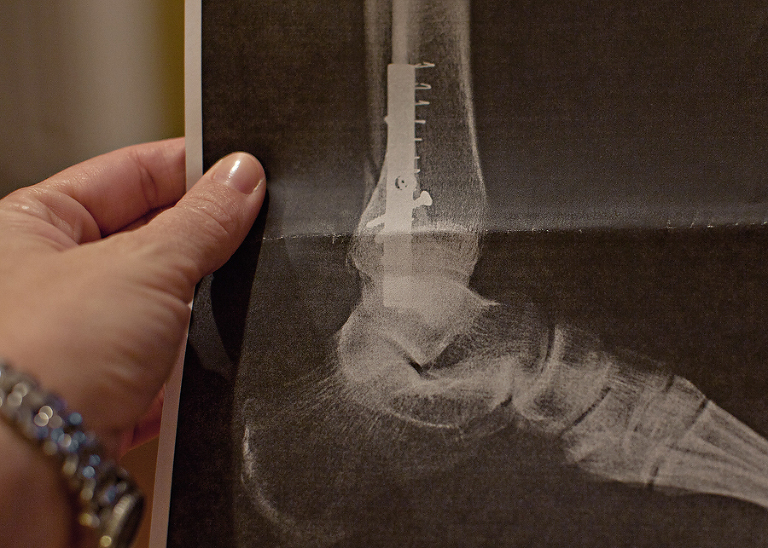

When he showed us the x-ray, I couldn’t help but ask about that one errant screw. It looked like the doc just dropped one in there by accident and forgot all about it.

He assured me that the errant screw had a purpose, and he didn’t seem like it bothered him that I was questioning his mad surgery skills. Come on, you know that screw looked wrong!!!.jpg)